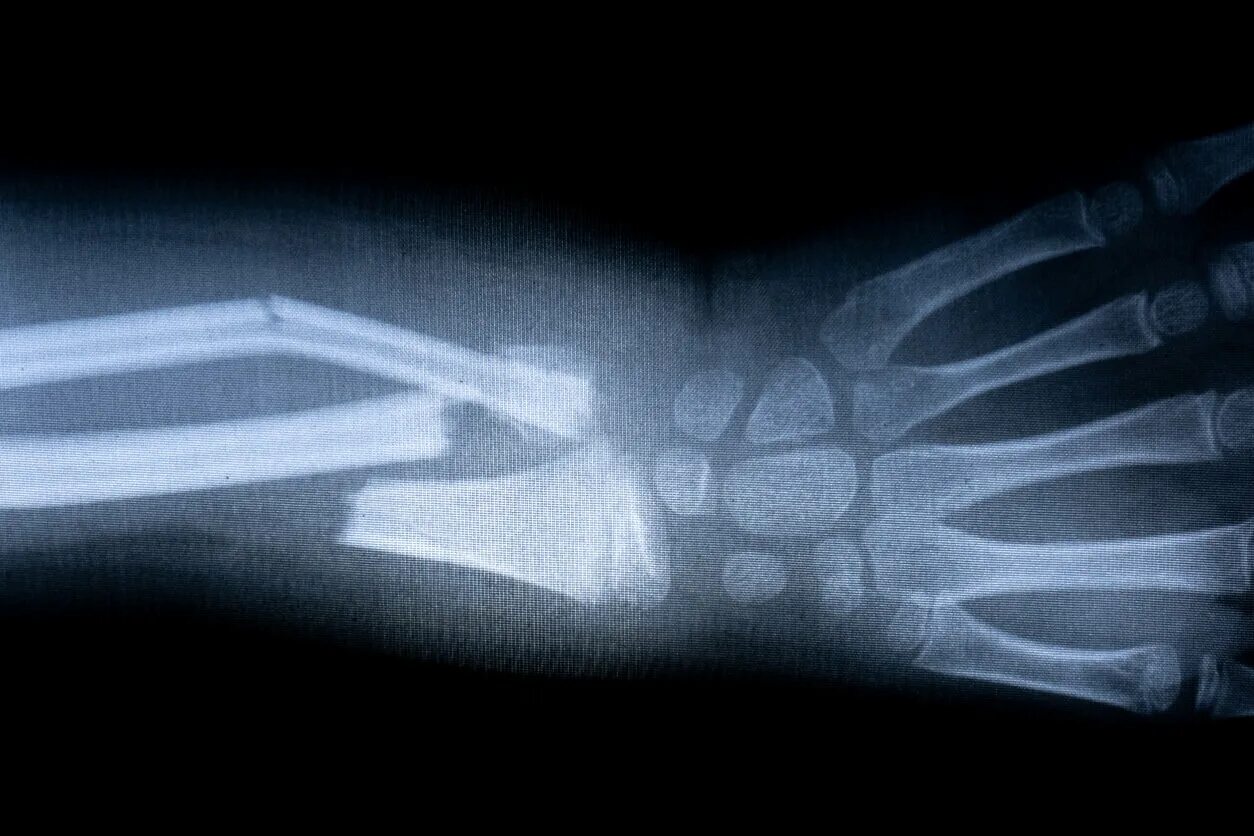

A fracture is a broken bone